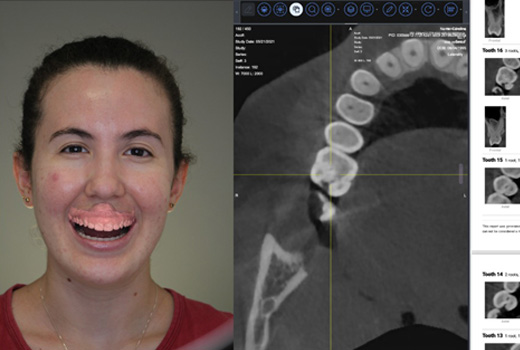

AI Diagnostics

Assess the patient’s radiological studies and view reports using CBCT images during your treatment planning.